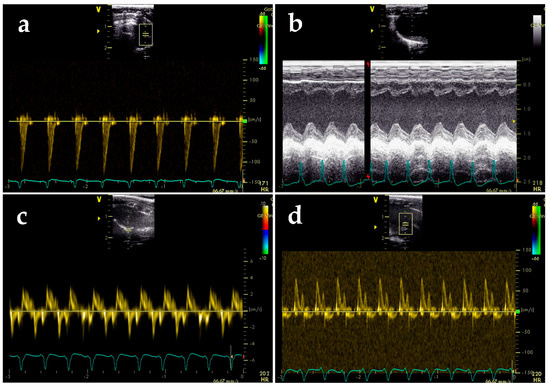

2.3. BGP-15 Enhances Diastolic Function Measured by Echocardiography

4.4. Echocardiography

4.5. Functional Vascular Assay